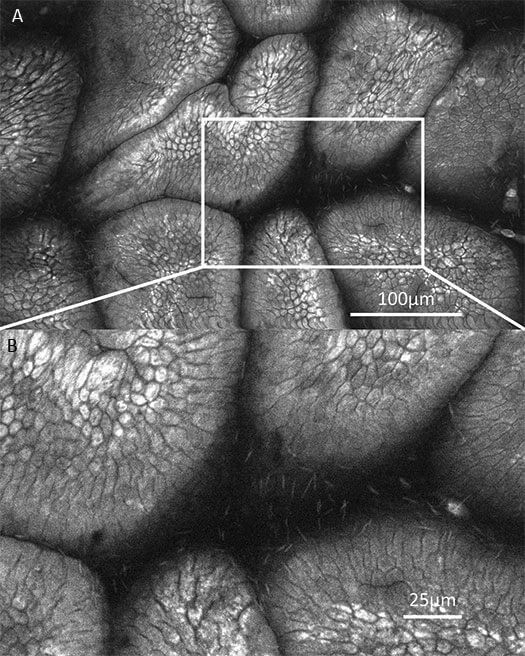

1、口腔癌OptiScan成像

左:正常組;中:癌前期組;右:癌變組。

注:Optiscan技術(shù)可以實(shí)時(shí)捕捉口腔黏膜的亞細(xì)胞細(xì)節(jié),而無(wú)需進(jìn)行活組織檢查。Scale bar=100μm。